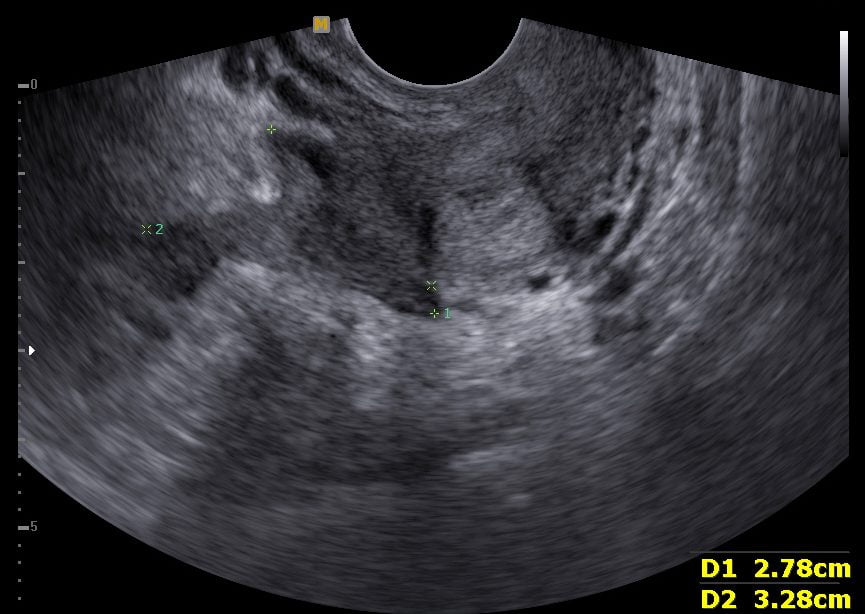

Imagem de ultrassonografia transvaginal demonstrando veias uterinas dilatadas e com mudança na direção do fluxo durante manobras provocativas, confirmando o diagnóstico de Varizes Pélvicas.